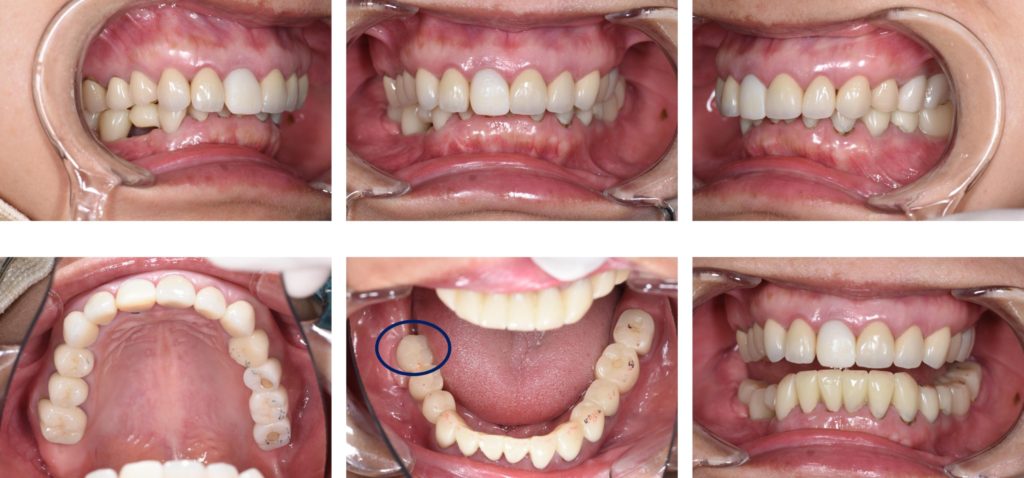

After

| 治療方法 | 当初は他院でインプラトができたいと言われた部分(右下)の骨造成処置後インプラト埋入手術を行なった。元々全てセラミックが入っていたが、全体的なバランス(咬合平面、咬合高径)、や歯の色に改善の余地があったため、患者との話し合いの上、可撤性のマウスピースでのトライ→接着性のトライ→セラミックへの置き換えを行なった(デジタルにて)。CADIAXにて術前、術中での顎運動の評価も行なった。 |